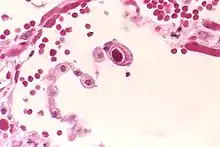

The term owl's eye appearance, also known as owl's eye sign, is used to describe a pattern resembling the shape of a real owl's eye that is found in the study of histology, radiology, and pathology cases. The pattern is used to analyze symptoms in patients within the medical field.

- Owl's eye appearance of inclusion bodies, which is highly specific for cytomegalovirus infection.[2]

- Owl's eye appearance of the entire nucleus – a finding in Reed–Sternberg cells in individuals with Hodgkin's lymphoma.

The owl's eye appearance has a relationship with Reed–Sternberg cells in regards to cytomegalovirus infection.[4] Owl's eye appearance was used as an indication of the presence of the cytomegalovirus for the following case studies.